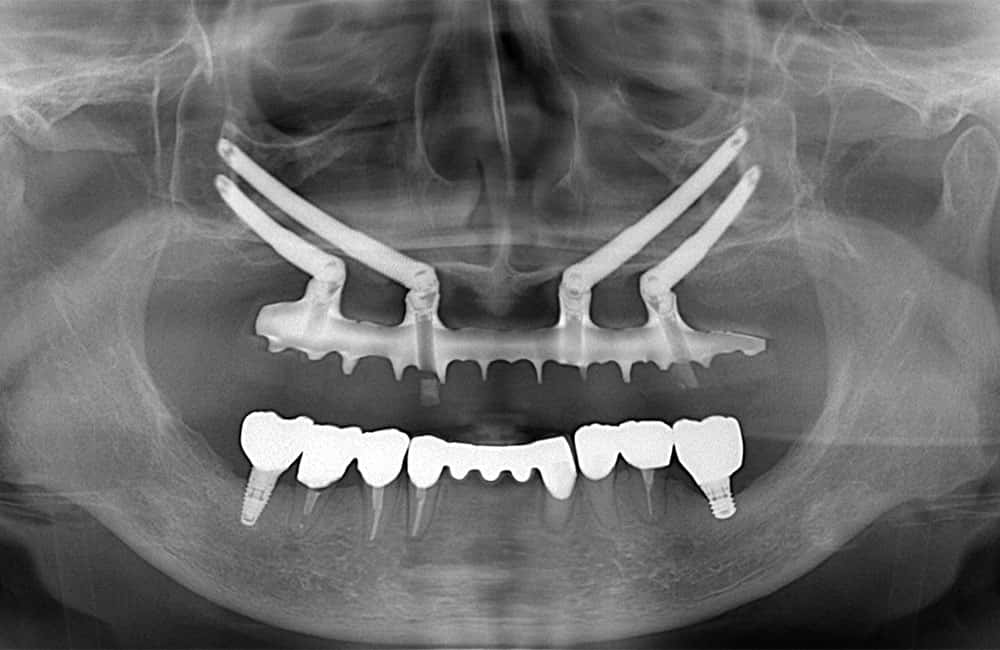

01All-on-4 Hybrid

前方は通常のインプラント、後方にザイゴマインプラントを用い上部構造を支える方法を、一般的にオールオンフォーハイブリッドと呼びます。

症例